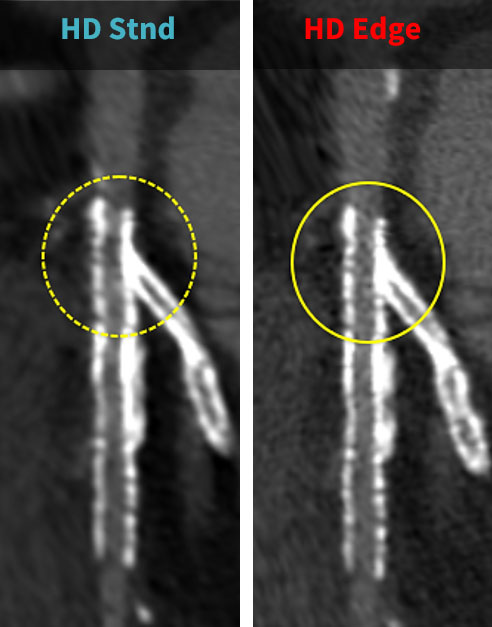

特にステント評価に対しては、高周波強調関数HD Edgeを使用することで、通常関数のHD Stndに比べてステント内腔の描出能が向上しました。これにより、冠動脈造影(CAG)と比較して、より精度の高い画像を医師に提供できるようになりました(図3、4)。空間分解能の評価としてTTFを計測すると、HD Edgeは高空間周波数帯域で優れた性能を示し、アンダーシュートが発生しない特性を持つことが確認できます(図5)。

患者様の体格によってはノイズが増加することがあるため、ステント留置後の症例に対しては必ずHD EdgeとHD Stndの二つのデータで用いて解析しています。胸部の診断を縦隔条件と肺野条件で行うように、冠動脈も非石灰化プラークや石灰化、ステント内腔評価など目的に応じた画像再構成を実施して診断する必要があると考えています。医師からもHD Edge画像を要望されるケースも増えており、ステント内腔の評価が不十分なためにCAGが実施されるケースは減少しています。

RevolutionApexElite_Minaminojunkanki05.jpg

(図3)

左:HD Stndで再構成した画像

右:HD Edgeで再構成した画像